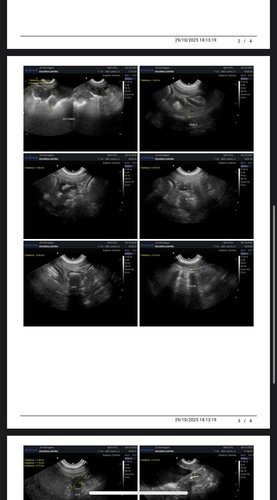

Alguns meses atrás realizamos exames e biópsia que teve como resultado hemangioma, um tumor benigno que poderia virar um tumor maligno chamado emangiossarcoma. Como são vários nódulos pelo corpo dela, existia chance de algum deles já ser maligno. Então nossa saída era fazer outros exames para poder começar uma eletroquímio, porém na ultrassom encontramos uma neoplasia de 14cm na parede do estômago, cisto no ovário esquerdo e pancreatite.

Já fizemos a gastrectomia para biópsia e castração, para agora acompanhar com ultrassom. Para um cachorro de grande porte e uma cirurgia delicada, o custo que já era alto ficou ainda maior. Felizmente está tudo correndo bem, ela está ótima para alguém que operou. Hoje, clinicamente ela está bem e não apresenta nenhum sintoma, então é o melhor momento para tratar a cuidar dela. Estamos com um veterinário de muita confiança para observar cada mudança com ela e aplicar vitaminas que são importantes para o imunológico dela. Mas ainda temos que terminar de pagar os custos dessa primeira primeira parte que passamos. Não pretendemos atingir metas, mas qualquer ajuda será recebida com muita gratidão! Se começarmos temos que ir até o final, pelo bem e carinho que temos por ela. Toda ajuda é bem vinda!